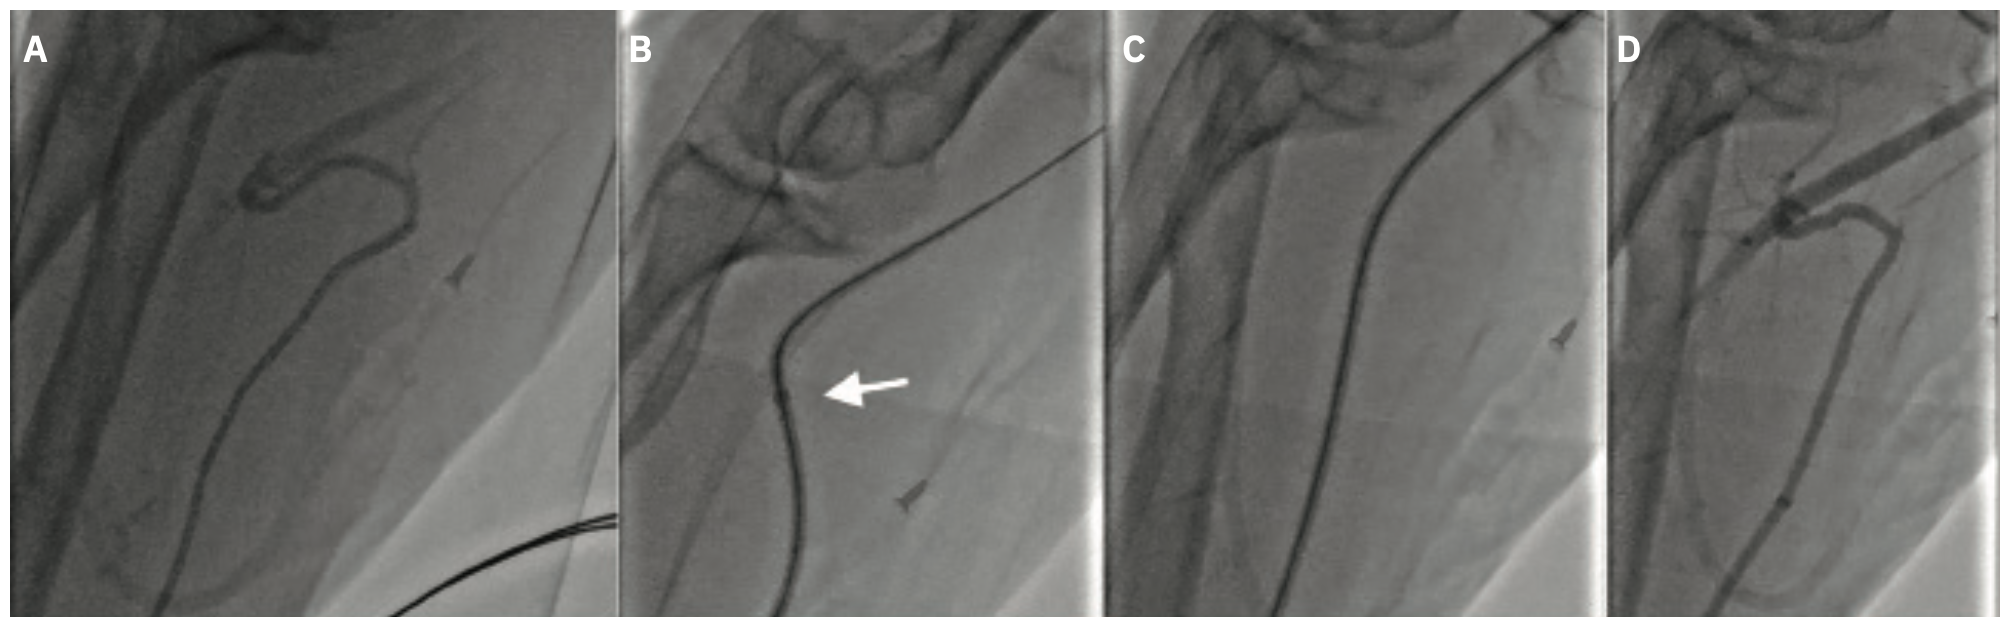

Ultrasound-guided right radial access was obtained and a 6F radial sheath was placed. There was difficulty passing an .035-inch guidewire and hence a radial angiogram was performed (Figure 2A), revealing a tortuous radial loop. We accessed the ascending aorta via the radial loop with a stiff angled Glidewire. The loop, however, did not straighten. We anticipated a lack of torque with diagnostic coronary catheters, and potential for severe spasm and or pain with the presence of the radial loop. We proceeded to cross the radial loop with a 6F 75 cm R2P™ DESTINATION SLENDER™ Guiding Sheath without any difficulties. The radial loop straightened with placement of the R2P™ DESTINATION SLENDER™ Guiding Sheath (Figure 2B-2C). A diagnostic coronary angiogram was performed without any difficulty and showed no obstructive coronary artery disease. The R2P™ DESTINATION SLENDER™ Guiding Sheath was pulled back proximal to the radial loop over the Glidewire and a final radial angiogram confirmed no trauma to the radial artery (Figure 2D).